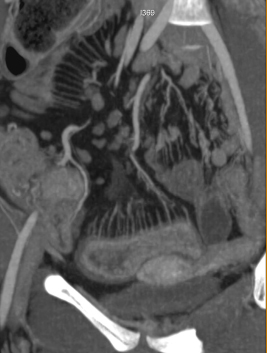

| Epaissisement parietale avec

oedeme de la sous muqueuse ( fleche rouge ) . Image

de fissuration legere peut se voyait un peut dans ce

cas . Maladie de Crohn de ileon en coupe TDM

coronale |

Signe de peigne " comb

sign " ( fleche jaune ) et epaissisement de la paroi

de ileon . Maladie de Crohn en phase aigue . Image

TDM . |